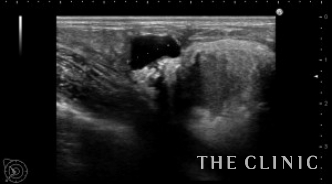

術前のエコーです。

右: 一部被膜が破れています